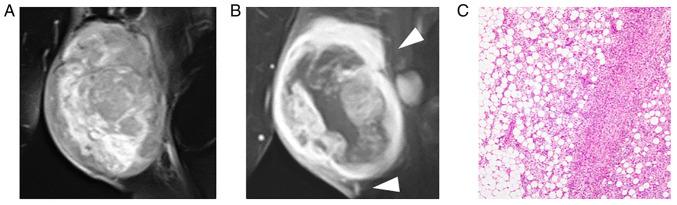

NTRK-rearranged spindle cell neoplasms (NTRK-RSCNs) are a new category of soft tissue tumors with gene fusions. The present study aimed to investigate the radiological features of NTRK-RSCNs and their association with histopathological findings. The present study included six patients with NTRK-RSCNs, whose fusion genes were confirmed using next-generation sequencing. All patients underwent surgery, and their diagnosis and clinical outcomes were investigated. In addition, the magnetic resonance imaging (MRI) features of all tumors and histopathological findings of the resected specimens were assessed. The present study included three women and three men, with a mean age of 22 years (range, 2-43 years). The gene fusions included four and two fusions. Three patients were preoperatively diagnosed with solitary fibrous tumors. One patient with fusion experienced local recurrence and distant metastases, whereas the other five patients had no local recurrence or metastasis. MRI revealed that all tumors were highly vascular with intra- and peritumoral flow voids of differing degrees. Furthermore, a partially ill-defined border, suggesting infiltration of tumors into the surrounding tissues, particularly fat tissue, was observed in five patients, which was confirmed by histopathological findings. In conclusion, NTRK-RSCNs are highly vascular tumors that can infiltrate the surrounding tissues. These findings suggested that NTRK-RSCNs should be considered in the differential diagnosis of highly vascular-rich mesenchymal tumors, including solitary fibrous tumors and alveolar soft part sarcomas. Furthermore, wide resection may be preferred to completely resect this type of tumor, considering its invasive nature.

神经营养酪氨酸激酶受体(NTRK)重排的梭形细胞肿瘤(NTRK-RSCNs)是一类新的伴有基因融合的软组织肿瘤。本研究旨在探讨NTRK-RSCNs的影像学特征及其与组织病理学结果的相关性。本研究纳入了6例NTRK-RSCNs患者,其融合基因通过二代测序得以确认。所有患者均接受了手术,并对其诊断及临床结局进行了调查。此外,还评估了所有肿瘤的磁共振成像(MRI)特征以及切除标本的组织病理学结果。本研究包括3名女性和3名男性,平均年龄22岁(范围2 - 43岁)。基因融合包括4例 和2例 融合。3例患者术前被诊断为孤立性纤维瘤。1例伴有 融合的患者出现局部复发和远处转移,而其他5例患者未出现局部复发或转移。MRI显示所有肿瘤血供丰富,瘤内和瘤周存在不同程度的血流空洞。此外,5例患者观察到边界部分不清,提示肿瘤浸润周围组织,尤其是脂肪组织,这一点经组织病理学结果证实。总之,NTRK-RSCNs是血供丰富且可浸润周围组织的肿瘤。这些发现提示,在鉴别诊断血供丰富的间叶组织肿瘤时,包括孤立性纤维瘤和肺泡软部肉瘤,应考虑NTRK-RSCNs。此外,鉴于其浸润性,广泛切除可能更有利于完全切除这类肿瘤。